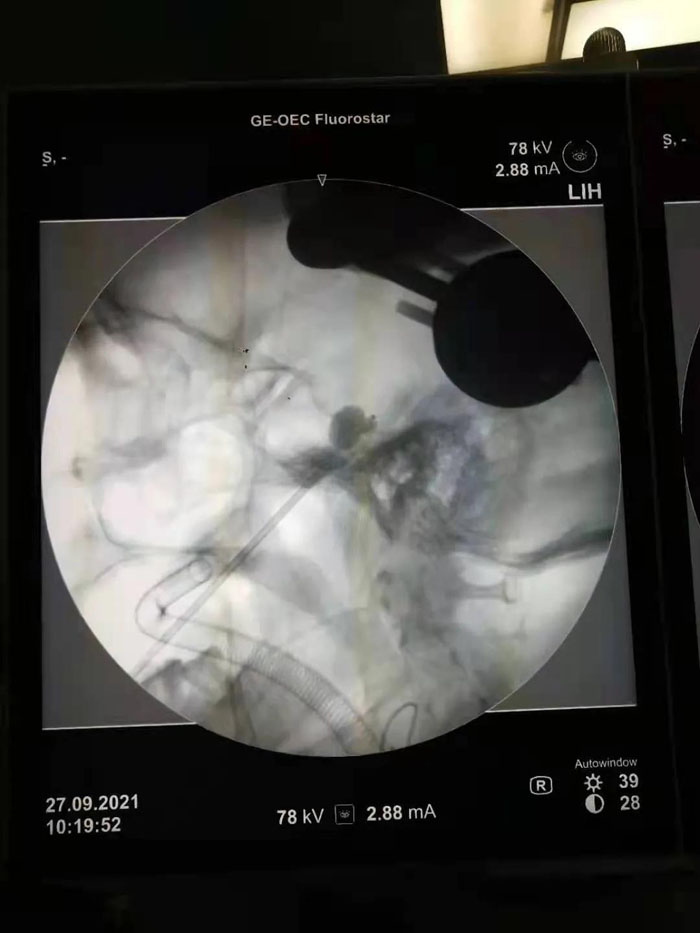

病例1.患者年近八旬,患有三叉神經(jīng)痛多年,疼痛發(fā)作起來痛不欲生,吃飯、洗臉都成了奢望。曾兩次到濟(jì)南某省級醫(yī)院行射頻、藥物注射等治療,無明顯效果。續(xù)繼軍主任團(tuán)隊術(shù)前仔細(xì)研判患者病情,認(rèn)為患者年齡大,開顱手術(shù)風(fēng)險較高。三叉神經(jīng)半月節(jié)球囊壓迫術(shù)具有微創(chuàng)、恢復(fù)快、費用低的優(yōu)勢,更適合老年患者及復(fù)發(fā)患者。但該手術(shù)需要精確定位,手術(shù)最大的挑戰(zhàn)是要把穿刺針準(zhǔn)確穿入近10cm外的卵圓孔,而該孔僅有3mm的大小,難度不亞于射擊比賽中“百步穿楊”。傳統(tǒng)方法只能在C形臂引導(dǎo)下徒手進(jìn)行,穿刺成功率低。在續(xù)繼軍主任指導(dǎo)下,丁鵬、吳開福主治醫(yī)師采用機(jī)器人輔助穿刺,術(shù)前驗證誤差僅為0.37mm,保證了一針穿刺到位,實際術(shù)中僅用10秒鐘即完成了穿刺操作,避免了重要血管、腦組織的損傷,大大降低了手術(shù)風(fēng)險。術(shù)后,患者面部疼痛即基本消失,2天后順利出院。